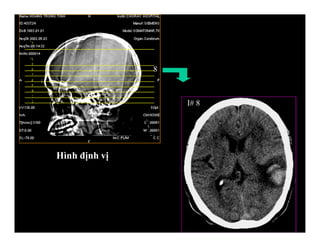

Trình bày trên phim

Hình định vị

Hình định vị

Hình CT

Khung hình

PHIM CT

Các thông số

I# 8

8